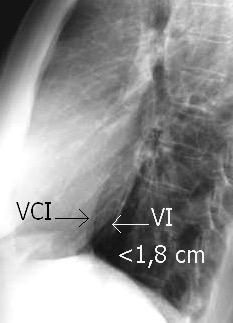

Diafragma izquierdo +/-16mm El ligamento pulmonar izquierdo (LPI) puede interrumpir la interfase normal pulmonar-diafragma obliterando un pequeño segmento

Proto AV,. The left lateral radiograph of the chest. Part One. Med. Radiogr. Photogr.1979.

Variante: Aire/grasa por delante de la VCI

Molinari F et al. Fat-containing Lesions in adult thoracic imaging. AJR.2011